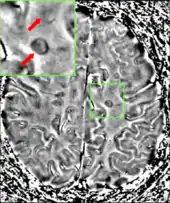

Magnetic resonance imaging (MRI) of the brain and spine may show areas of demyelination (lesions or plaques). Gadolinium can be administered intravenously as a contrast agent to highlight active plaques, and by elimination, demonstrate the existence of historical lesions not associated with symptoms at the moment of the evaluation.[72][73]

Central vein signs (CVSs) have been proposed as a good indicator of MS in comparison with other conditions causing white lesions.[74][75][76][77] One small study found fewer CVSs in older and hypertensive people.[78] Further research on CVS as a biomarker for MS is ongoing.[79]